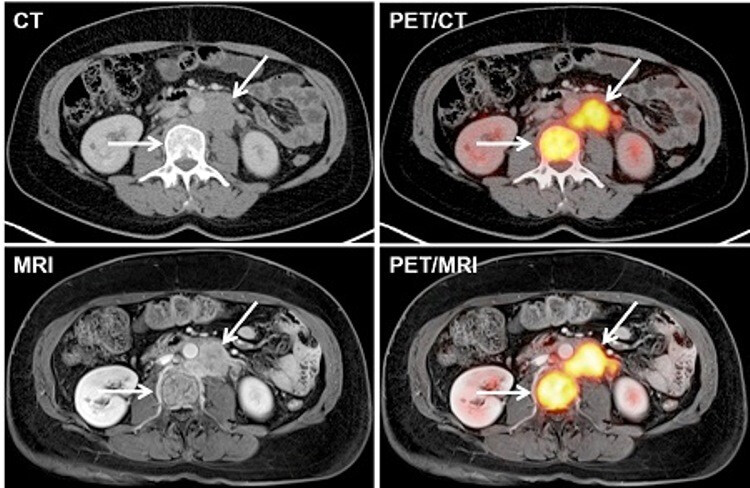

MRI, CT, PET-CT: nézze meg, mire számíthat a vizsgálatokon!